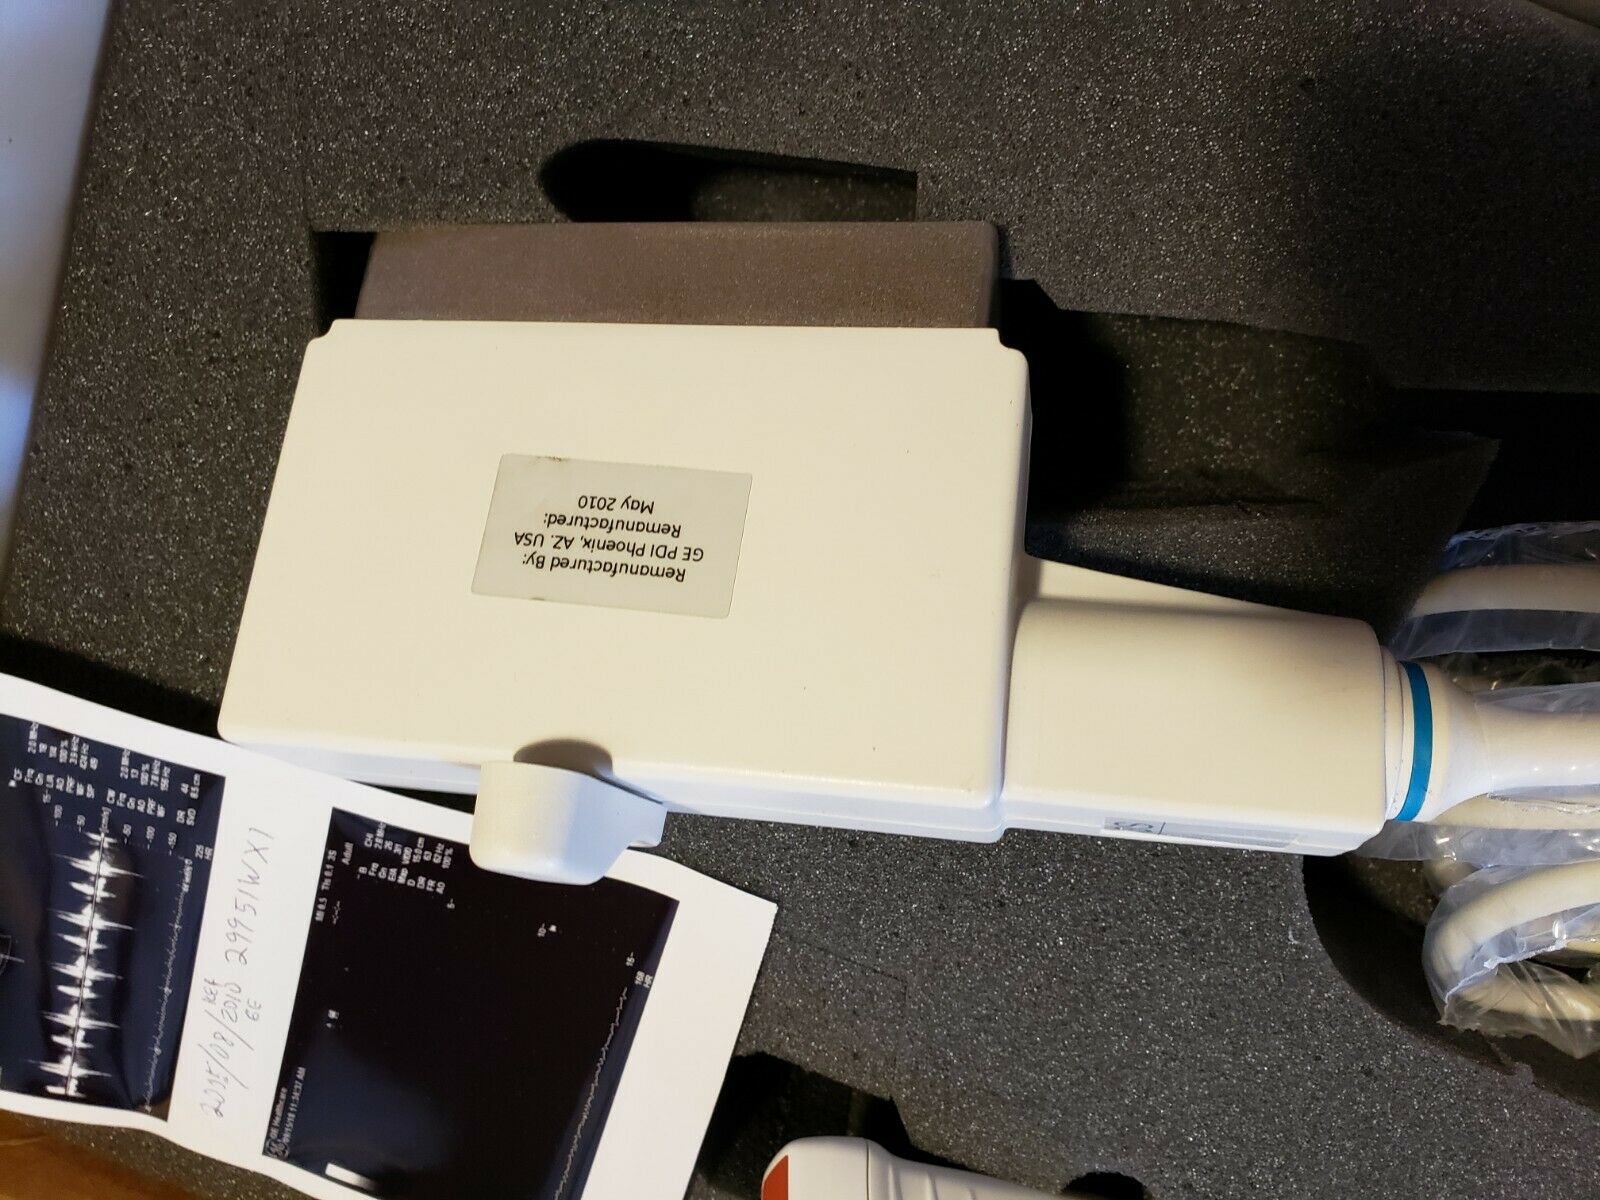

DIAGNOSTIC ULTRASOUND MACHINES FOR SALE

GE 348C 2197480 ULTRASOUND TRANSDUCER PROBE

Sale price$ 3,599.78